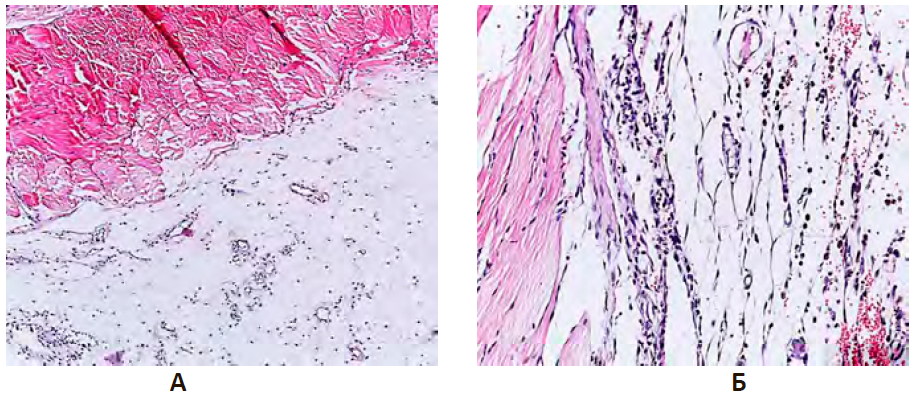

При гистологическом исследовании тканей плевральной полости на 30-е сутки в группе негативного контроля наблюдался выраженный отек соединительной ткани, обильно инфильтрированной нейтрофилами, единичными плазмоцитами и макрофагами. Мезотелий висцерального и париетального листков не визуализировался, между тонкими тяжами соединительной ткани определялся экссудат, который по своему составу был представлен преимущественно нейтрофилами. Выявлено диффузное пропитывание и утолщение плевральных листков за счет выраженного отека и обильной нейтрофильной инфильтрации. Сосуды микроциркуляторного русла были умеренного кровенаполнения, с явлениями периваскулярного отека, что гистологически проявлялось разволокнением сосудистой стенки и наличием оптически пустых периваскулярных пространств (рис. 13А).

У животных группы сравнения (на фоне введения доксициклина) отмечалось наличие единичных незрелых спаек в плевральной полости. Спайки были сформированы рыхлой волокнистой соединительной ткани, при этом тонкие соединительнотканные волокна имели различное направление, между которыми выявлялось обилие умеренно полнокровных сосудов. Между волокнами соединительной ткани четко визуализировалось скопление фибробластов, которые имели округлые ядра и незначительное количество цитоплазмы. Кроме этого определялась лимфоцитарная инфильтрация с наличием единичных плазматических клеток. В плевральных сращениях определялись гранулы гемосидерина, а также крупные клетки с наличием в цитоплазме бурого пигмента (сидерофаги). Обращало на себя внимание, что сосуды микроциркуляторного русла были выстланы эндотелиоцитами с округлым ядром, что свидетельствовало о «раздражении» эндотелия и являлось морфологическим признаком эндотелиальной дисфункции (рис. 13Б).

В опытной группе с биологическим потенцированием адгезиогенеза в плевральной полости плазмой, обогащенной тромбоцитами зарегистрировано образование множественных спаек с наличием строго ориентированных соединительно-тканных волокон, где определялись фибробласты и фиброциты с вытянутым ядром и незначительным количеством цитоплазмы. Визуализировались единичные сосуды с эндотелием типичного строения. Морфологические признаки воспаления были минимальны и характеризовались наличием единичных лимфоцитов и плазматических клеток (рис. 13В).

Рисунок 13 – Экспериментальная эмпиема плевры на 30-е сутки эксперимента

Примечание: А. Группа НКэп. Б. Группа сравнения. В. Опытная группа (PRPэп) при введении плазмы, обогащенной тромбоцитами. Зрелая спайка в плевральной полости крыс с наличием ориентированных соединительно-тканных волокон, незначительным количеством лимфоцитов на фоне хронической эмпиемы плевры. Окраска гематоксилином и эозином. Ув. ×400.